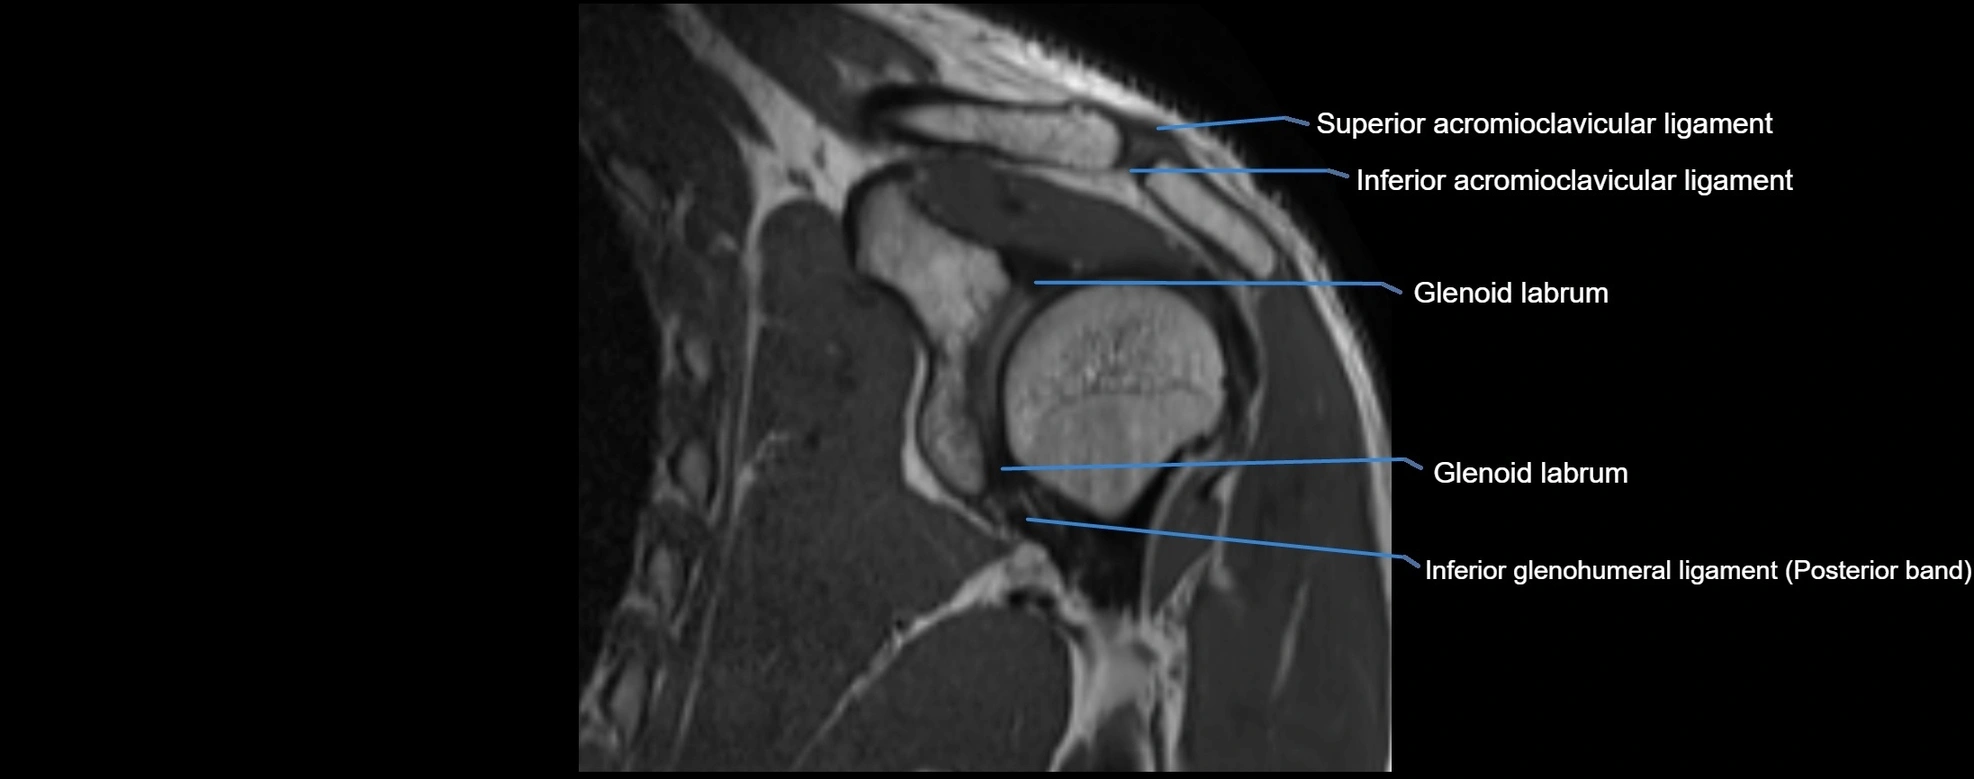

MRI images

image